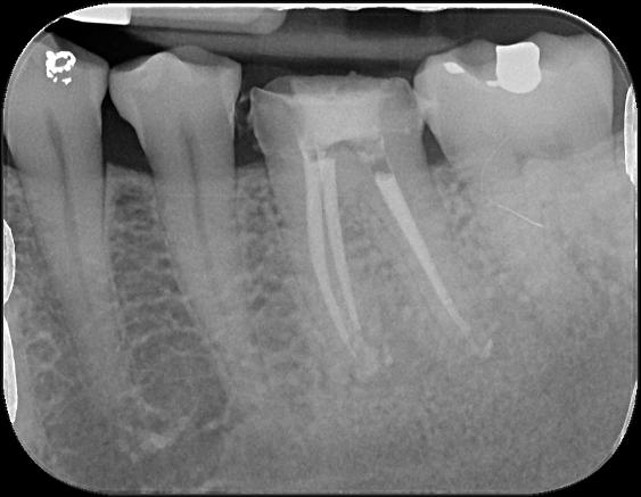

根管重治療與充填

治療後,根管充填緻密